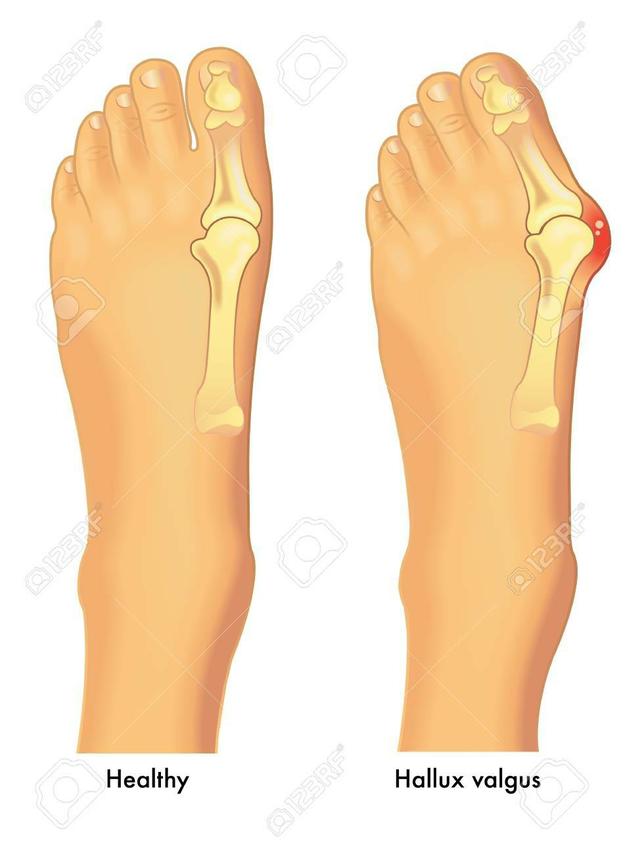

拇趾外翻是一种进行性足部畸形,其中第一跖趾关节(MTP)受到影响,经常伴有严重的功能残疾和足部疼痛。该关节逐渐半脱位(MTP关节的侧偏),导致第一跖骨外展,而指骨内收。这通常导致内侧软组织和骨性突起,即所谓的拇囊炎(第一跖骨头背内侧的外生骨)。在晚期,这些变化会导致疼痛和功能缺陷:即步态受损(侧移和后移重心,后期足跟抬高,单侧肢体平衡下降,旋前畸形)。拇外翻在整个人群中的发病率很高(18-65岁的成年人占23%,65岁以上的成年人占35.7%)。女性(30%-13%)和老年人(35.7%)患病率较高。

在这种足部畸形中,随着第一跖骨远端向内侧漂移和近端指骨向外侧偏移,内侧隆起变得突出。第一MTP半脱位,导致拇趾向外侧偏,第一跖骨远端内侧移位,第一跖骨头骨质增大。

在纵向将近节指骨和第一跖骨中轴线之间形成的角度称为拇外翻角(hallux valgus angle,HVA)。小于15°视为正常。大于等于20°的角度视为异常。45-50°的角度被认为是严重的。